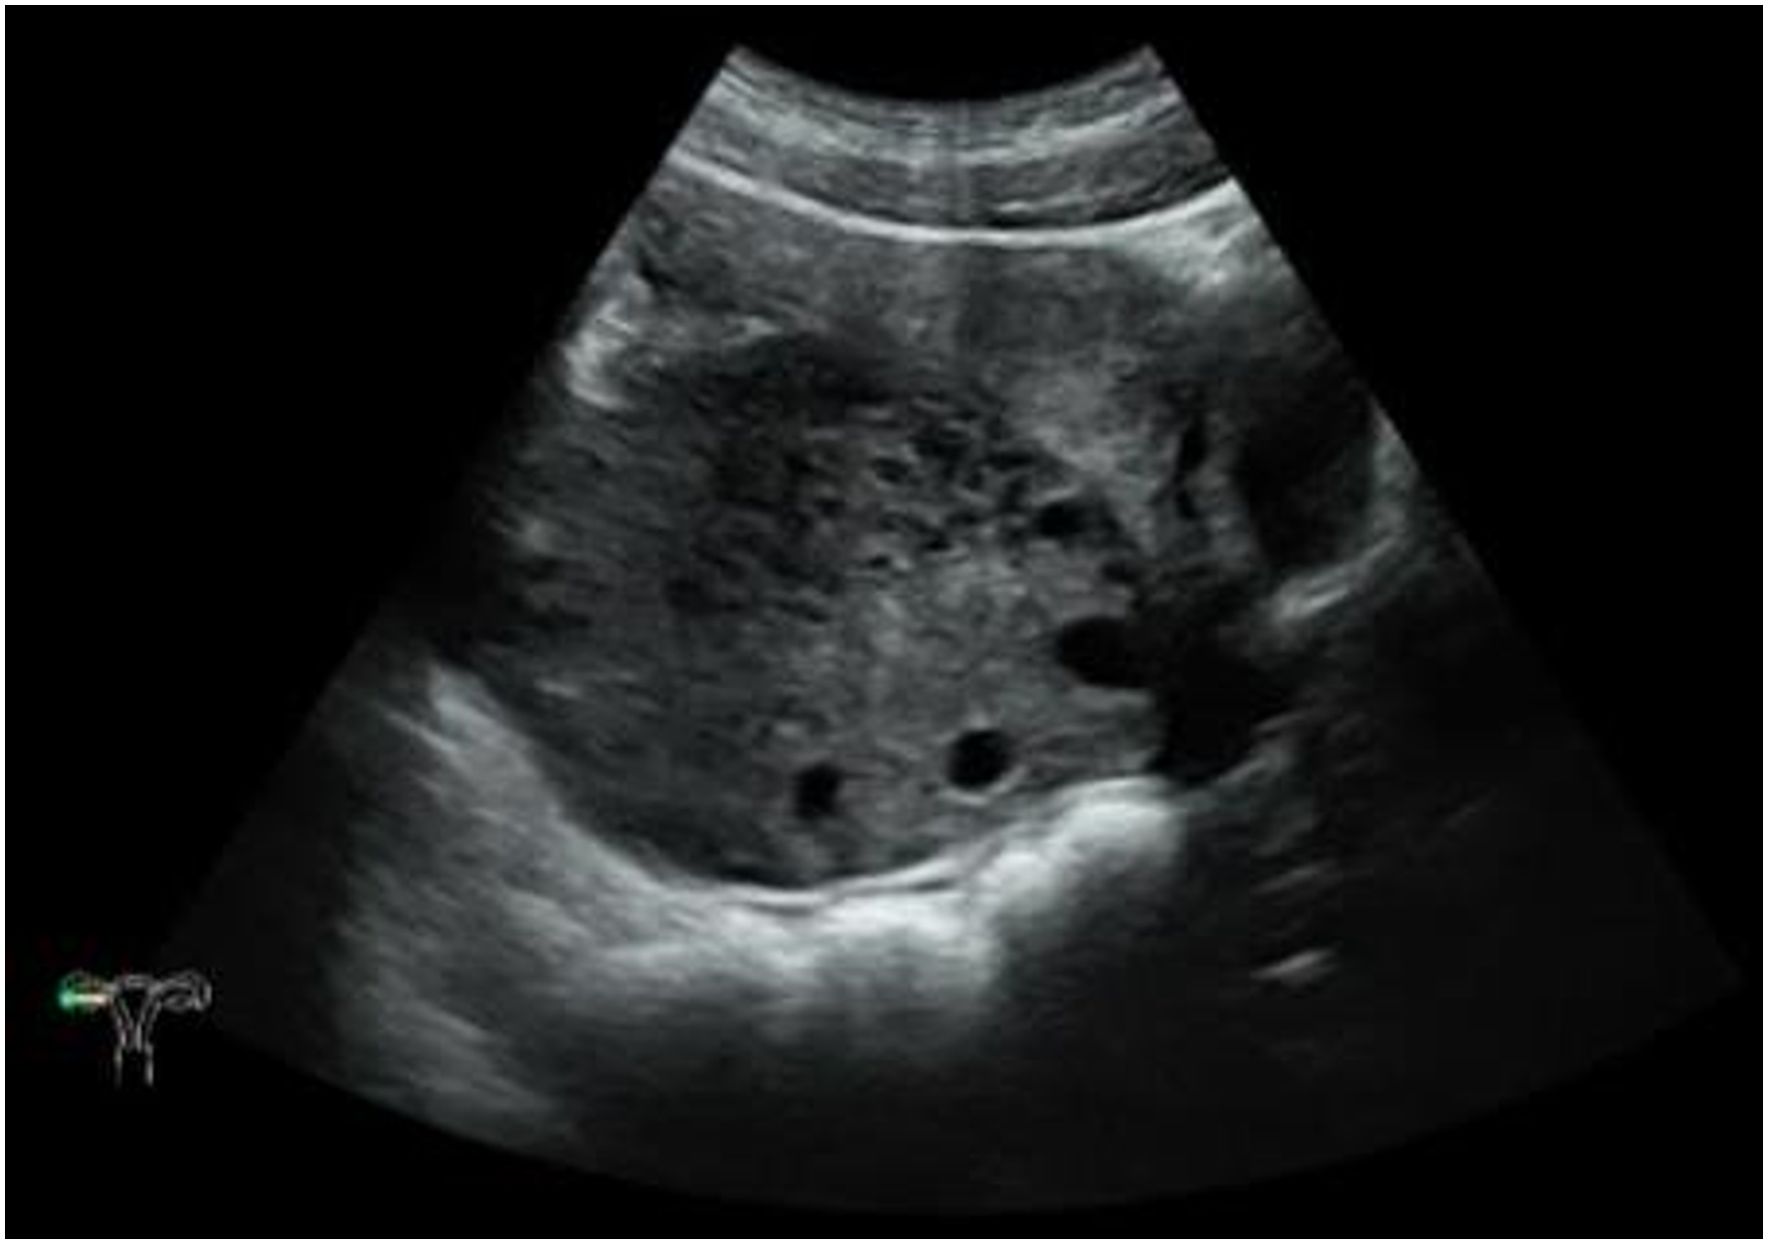

A female patient aged 14 years 7 months complained of mild lower abdominal pain and a prolonged menstrual cycle of more than 2 months. Menarche occurred at 14 years of age, with a menstrual period of 4 – 5 days and a cycle of 30 – 80 days. Physical examination revealed a widespread distribution of dense hair, including on the vulva, below the umbilicus, and around the anus. A large mass, approximately 10 cm in diameter, was palpated posterior to the uterus. Transabdominal ultrasound showed a heterogeneous, weakly echogenic right adnexal mass measuring approximately 8.6×5.9×9.0 cm, with multiple anechoic areas and blood flow signals (Figure 2). Magnetic resonance imaging (MRI) showed a mass measuring approximately 4.7×9.1×6.5 cm posterior to the uterus, which had a low signal on T1 weighted images and a heterogeneous high signal on T2 weighted images (Figure 3). Multiple small cystic shadows were observed. Tumor markers and sex hormone levels were within normal limits, including: ThCG<2.0 mIU/ml, CA125 7.3 U/ml, CA19-9 24.3 U/ml, CA15-3 7.0 U/ml, CEA <0.5 ng/ml, AFP 1.9 ng/ml. The patient underwent surgery via TU-LESS.

Figure 2. Transabdominal ultrasound findings. There was a heterogeneous, hypoechoic right adnexal mass with multiple anechoic areas.